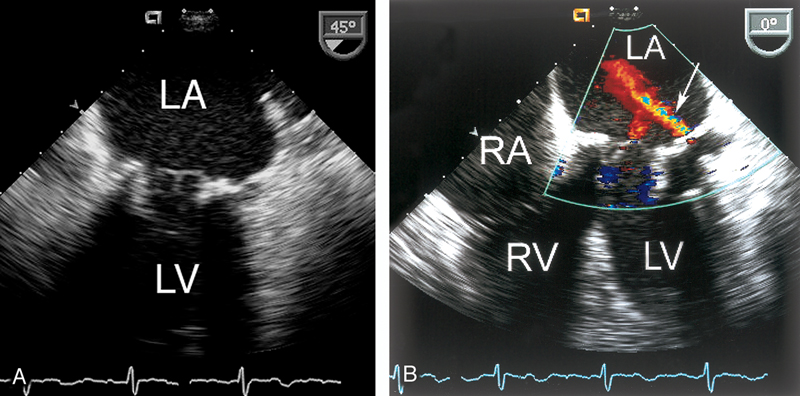

فحوصات تشخيصية لبعض امراض القلب والشرايين التاجية